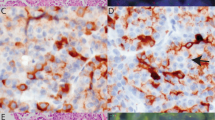

RET rearrangements in microcarcinomas were analyzed by dual color FISH using a probe that encompasses the RET gene along with an α-satellite probe that specifically recognizes centromere 10. In normal thyroid follicular cells, fluorescence microscopy revealed two signals corresponding to the RET gene associated with the two chromosome 10 centromere signals. The tumors that carried RET/PTC1 or RET/PTC3 rearrangements showed one signal associated with one of the centromeres and two signals in the proximity of the homologous centromere (Fig. 1, c and d). In the case of RET translocations (eg, RET/PTC2), the third signal was randomly distributed in the nuclei (data not shown). In cells that carried a trisomy for chromosome 10, the three RET signals were coupled with the three centromere 10 signals (Fig. 1e).

Histopathological and fluorescence in situ hybridization (FISH) analysis of microcarcinomas. a to b, Hematoxylin and eosin staining of a microcarcinoma (×100 and ×400, respectively). c to e, Status of the proto-oncogene RET in thyroid microcarcinoma nuclei. RET cosmids were labeled with biotin and detected with fluorescein-conjugated avidin (green), whereas the α-satellite DNA for centromere 10 was labeled with digoxigenin and detected with anti-digoxigenin-rhodamine Fab fragment (red). c to d, Microcarcinomas showing an inversion involving the RET gene. Filled arrow indicates the rearranged copy of RET (inversion), and the empty arrow indicates nuclei carrying two apparently normal copies of RET. e, Nucleus harboring chromosome 10 trisomy. f, Nuclei of microcarcinoma no. 21 hybridized with α-satellite DNA for centromere 6 (green) and centromere 12 (red) are trisomic for both chromosomes.

Two microcarcinomas (t.12 and t.21), both surrounded by adenomas, carried three copies of RET and three copies of chromosome 10 centromere (Fig. 1e). Subsequent hybridization with α-satellite probes for centromere 6 and 12 confirmed trisomies for these chromosomes as well (Fig. 1f). Parallel histopathological analysis of the two samples showed that trisomies were present both in the microcarcinoma and in the follicular adenoma surrounding it.